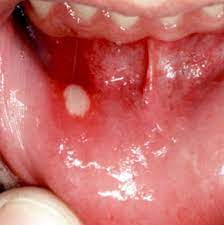

▣ 설암 증상

- 3주 이상이 지나도 낫지 않는 입 안의 궤양 (입 안 점막이 헐거나 파인경우)

일반적으로 가장 흔한 원인은 아프타 구내염과 같은 염증 때문이다. 이러한 구내염 때문에 한 군데에 생긴 궤양은 대개 1 ~ 2주 내로 없어지지만 심한 경우에는 다른 부위에 또 옮겨가기도 한다. 그러나 한 군데에 생긴 궤양이 3주가 되었는데도 아물지 않는다면 일반적 염증이 아닐 수 있으므로 병원을 방문해 보는 것이 좋다.

- 구강 점막의 적색 혹은 백색 반점

볼이나 혀에적 색 혹은 백색 반점이 생긴 경우에도 대부분은 원인을 잘 모르거나, 만성 자극에 의하여 점막에 변화가 생겨 발생한 일시적인 증상일 가능성이 높다. 그러나 이러한 점막의 변화는 드물게 암의 초기 증상이거나 암으로 변하는 전단계일 수 있다. 그러므로 이전에 진단 받은 적이 없는 경우라면 전문의의 진료를 받는 것이 좋고, 오래된 반점인 경우 최근에 더 두꺼워지거나 헐거나, 범위가 넓어지는 경우에는 조직 검사를 받아 보는 것이 좋다.